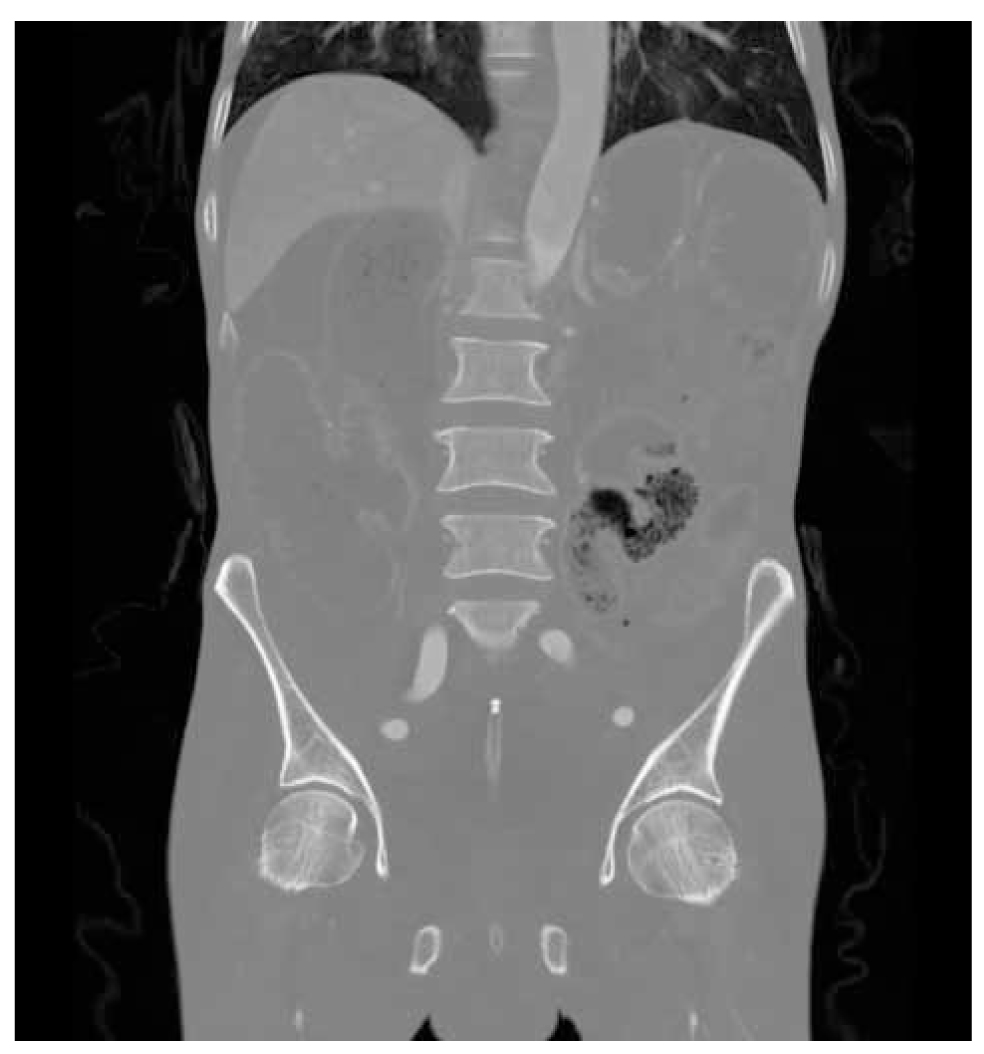

A 58-year-old male patient presented at the outpatient clinic with dyspeptic complaints. The patient had complaints of dyspepsia and upper gastrointestinal pain that had been ongoing for approximately five months. In the upper gastrointestinal system endoscopy, an ulcer with irregular borders, fragile to touch and malignant appearance was observed, which extended towards the greater curvature towards the proximal posterior wall of the corpus and the middle of the corpus. The histopathology report was evaluated as adenocarcinoma. Since no distant metastasis was observed on thoracoabdominal computed tomography (Figure 1), the decision to operate was made. Colonoscopy was not planned because the patient had no signs of constipation. Preoperative hemoglobin value was 12.9 g/dL and albumin value was 39.9 g/L. The patient received 4 cycles of chemotherapy with the FLOT regimen before surgery and 4 cycles after surgery. Subsequently, the patient underwent total gastrectomy, roux-n-y esophagojejunostomy and D2 lymph node dissection due to gastric cancer. The histopathology report was evaluated as gastric adenocarcinoma (T4aN3a) and intestinal type adenocarcinoma. There was no tumour in the surgical margins in histopathology. In histopathology report 36 lymph nodes were harvested and there was metastasis in nine lymph nodes. No postoperative complications developed and the patient was discharged on the 7th postoperative day. At three months after the surgery, the patient, who had no additional pathology, was admitted to the emergency room with ileus findings. On physical examination, there was widespread abdominal distension. Abdominal tomography showed widespread dilatation and air-fluid levels in the bowel loops. The patient underwent emergency surgery. During exploration, a mass lesion was observed in the proximal rectum, completely obstructing the lumen. There was no peritoneal carcinomatosis. Low anterior resection and loop ileostomy were performed. No postoperative complications were observed and the patient was discharged on the seventh postoperative day. The histopathology report of the case was evaluated as rectal metastasis of gastric cancer. The patient subsequently received adjuvant chemotherapy. The patient died four months after the second surgery due to poor general condition.

Figure 1. ct of the patient.